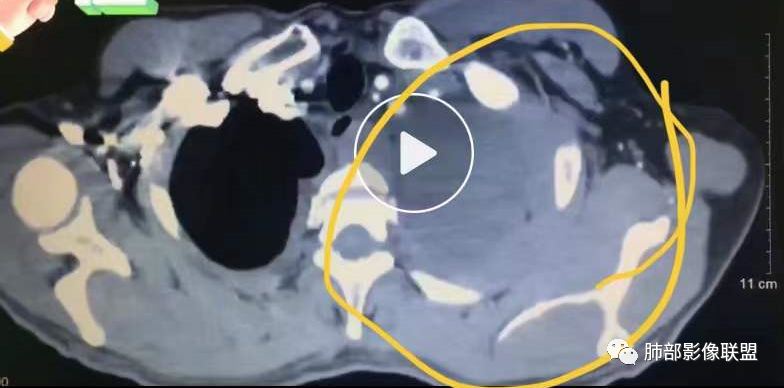

目前的图:主要是胸部的病灶。胸膜弥漫斑块状增厚。强化明显,内部血管漂浮。前纵隔部分病灶强化偏低。

累及多个腔隙、特别是后纵隔、胸膜为主

常规淋巴瘤、胸膜间皮瘤要警惕

有一个疑问,就是后纵隔那个是纵隔的吗,还是胸膜的

我把这个征象给忽略了,感觉很奇怪的病例。事后诸葛亮一下。这里的弥漫性,连续性增厚,有点特异性,还是要考虑到恶性间皮瘤的可能性的。胸膜转移瘤,不会这么连续性的不规则增厚。食管管腔是存在的,而且是推移明显,食管来源的话这种表现的最常见就是平滑肌瘤,不太符合。另外用小细胞解释腹腔病变感觉有点牵强,而且食管推移这么的明显,用淋巴瘤不好解释左心膈脚的这个软组织。没公布答案的时候,我一直在拿不准它到底是个啥。

2.影像学特点:病变范围相当广泛,多发块状影累及纵隔、胸膜、前胸壁(胸大肌下)、前上腹壁等。胸膜弥漫性斑状增厚为主,明显强化,纵隔旁椭圆形块影较密实,沿胸膜分布趋势,未见支气管等结构进入。后纵隔块影较大,占位效应明显,肺静脉受累狭窄。双侧胸腔积液。